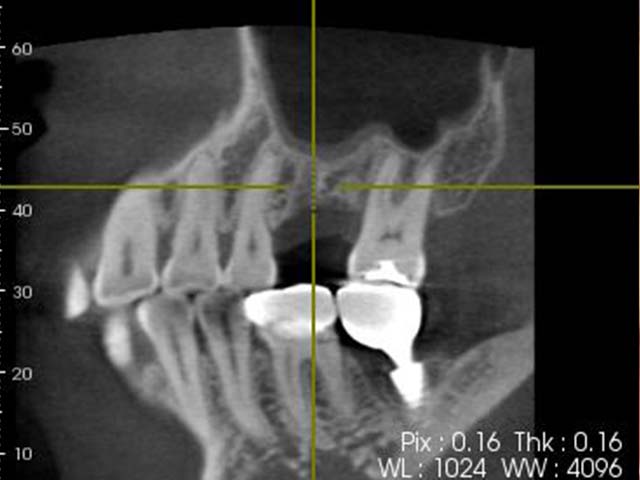

鼻竇增高術(垂直)+植牙 首頁 案例分享 人工植牙 鼻竇增高術(垂直)+植牙 鼻竇增高術(垂直)+植牙 術前評估 PRF(使用法國離心機,萃取出有益於傷口癒合的血小板,並加以濃縮) 鼻竇增高術 從植牙傷口置入萃取的PRF,將鼻竇往上抬升,再植入骨粉,以利植牙。 電腦斷層—術前,術中,假牙完成